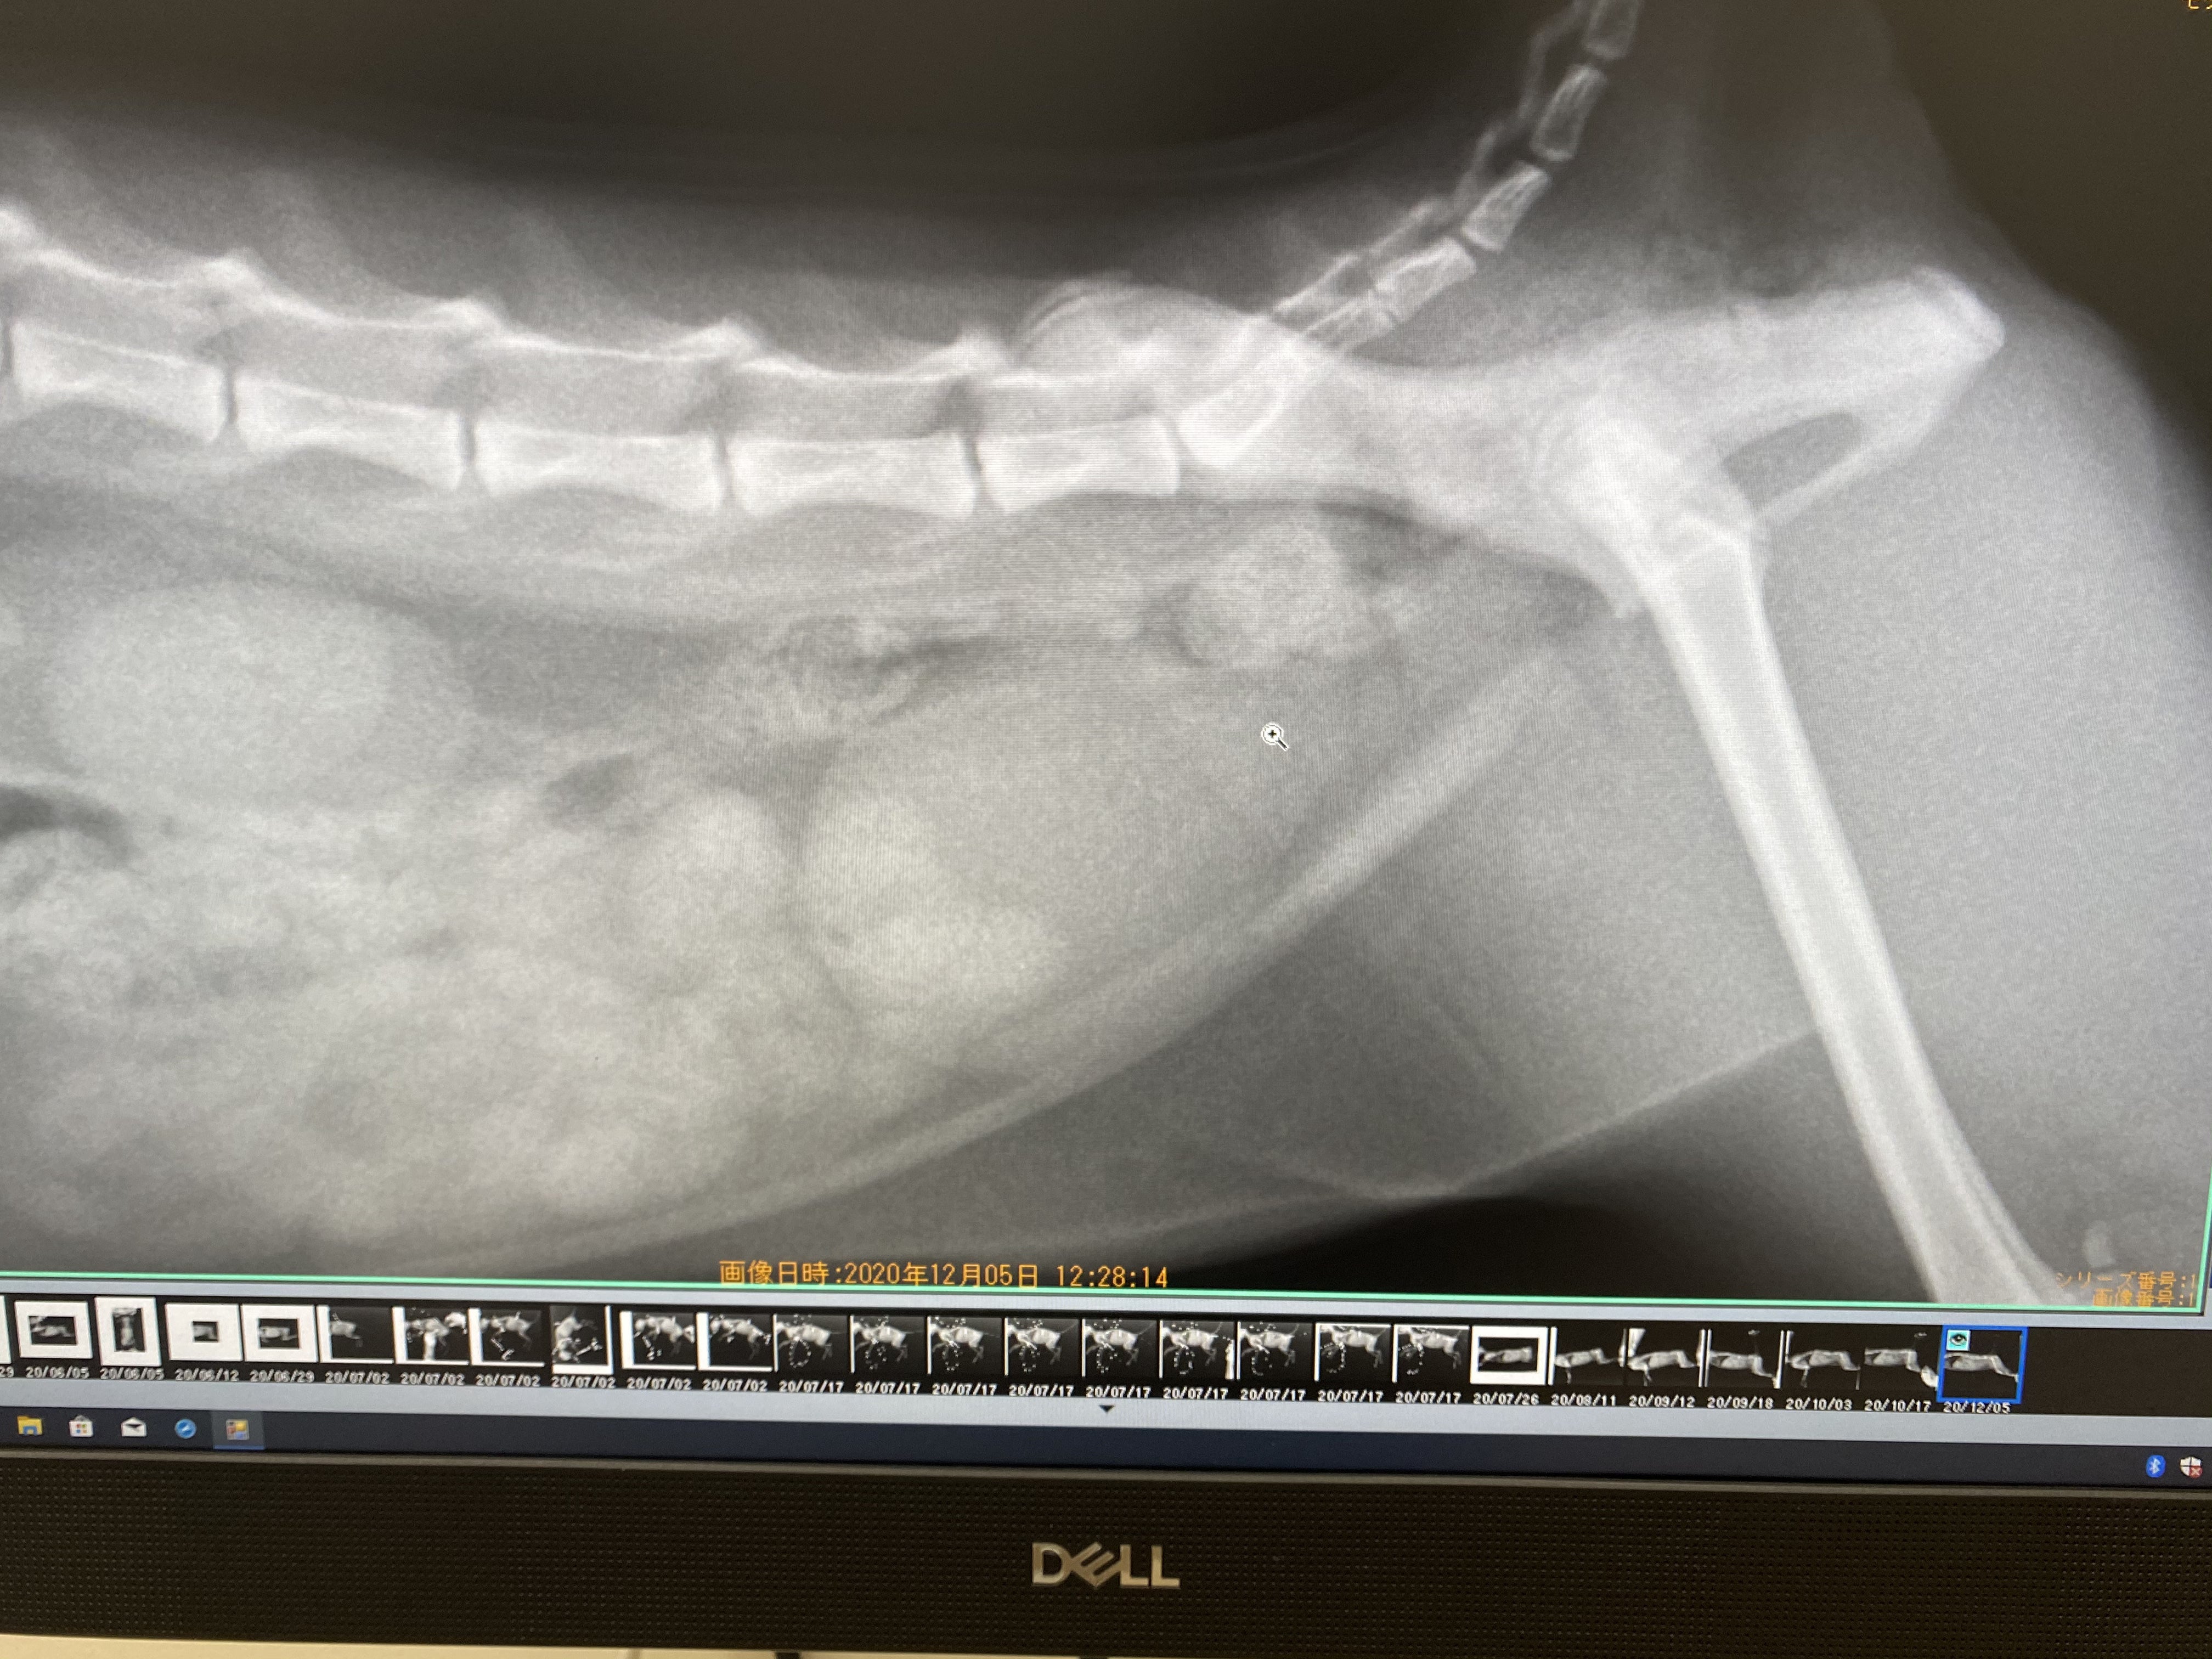

12月3日の受診で撮影された最新のレントゲン写真です。

背骨の関節の長さより腸内の直径が小さくなっており、巨大結腸症が解消されているのがわかります。

また、うんちも順調に出せているようです。